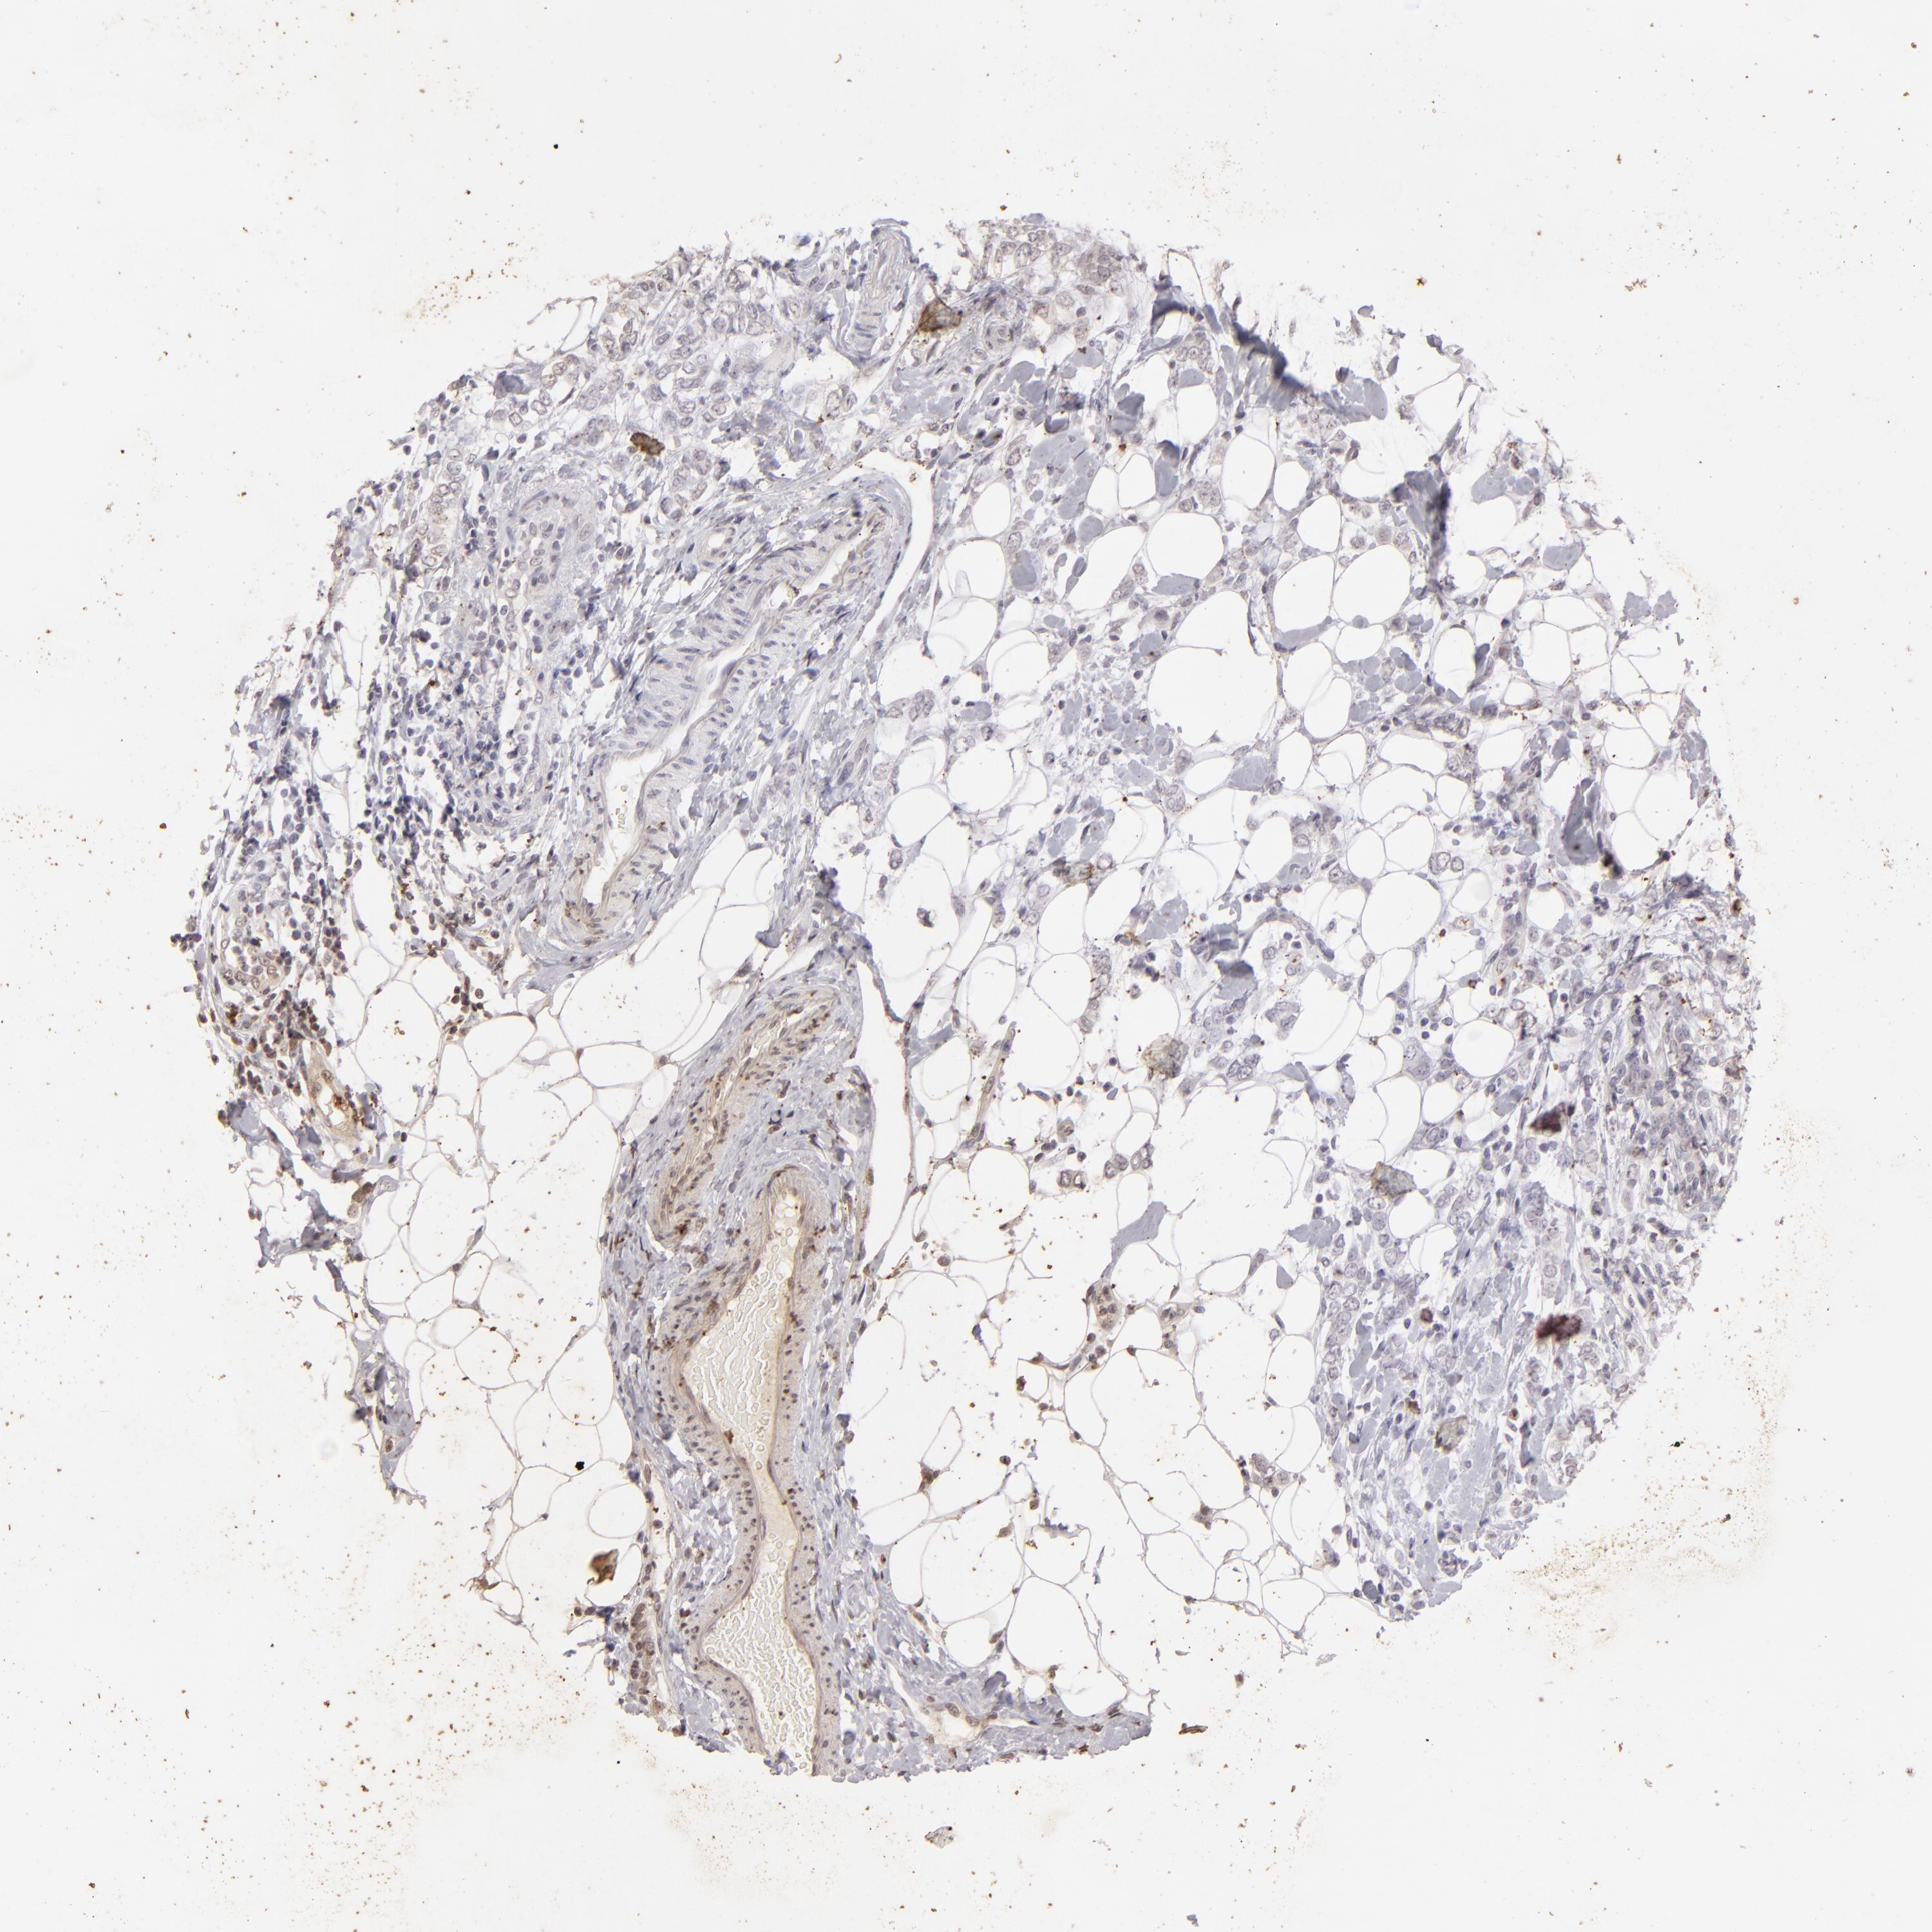

CANCER BREAST CANCER Show tissue menu

BRCA TCGA BRCA VALIDATION PROTEIN EXPRESSION

ANTIBODIES

AND

VALIDATION